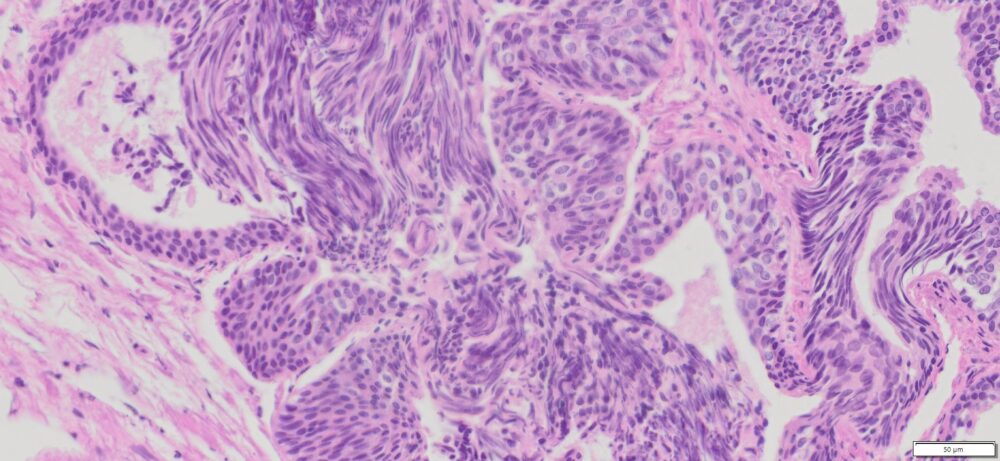

Description

| Tissue | Pathology Diagnosis | Gender/Age (year) | % Tumor area | Tumor Grade | TMN Stage | IHC Data |

| Human Rectum | Moderately differentiated colonic adenocarcinoma with 40% mucinous component | Male/59 | 20% | II | pT4apN1bpMx | NA |

Images for H&E Stain and IHC